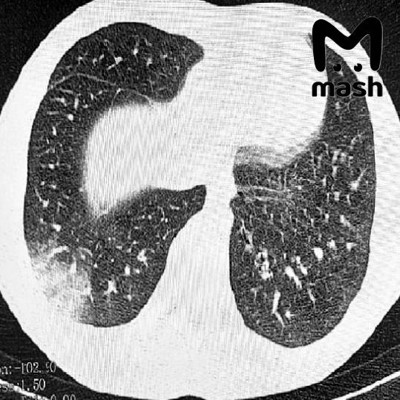

0Диагноз EVALI одному из пациентов уже поставили официально. У другого — «токсическое воздействие курительных смесей на центральную нервную систему». Пример пострадавших лёгких — на фото.

«Попкорновой болезнью» называют облитерирующий бронхиолит — заболевание, поражающее бронхиолы. Проявляется в виде воспаления, образования рубцов, сужения бронхиол. Заметить его можно при прослушивании лёгких, которые издают звук, напоминающий треск лопающегося попкорна.

Впервые EVALI диагностировано в 2019 году в США. Сегодня медицина не имеет эффективного лечения для этой формы бронхиолита. «Болезнь вейперов» может перейти в синдром острой дыхательной недостаточности, смертность от которого 30–50%. Также она повышает риск развития астмы на 30% и хронической обструктивной болезни лёгких на 75%.